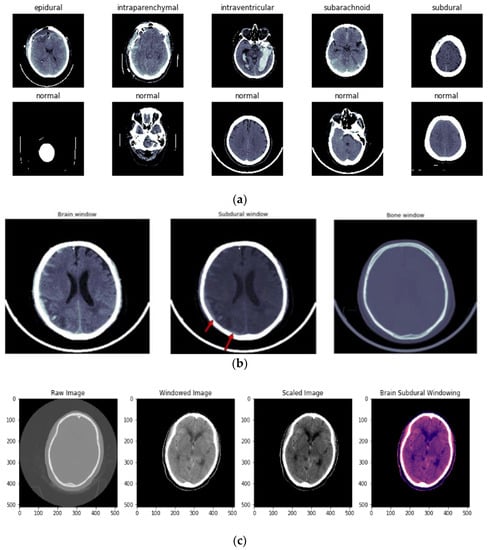

The first step in preparing the dataset was to convert intensities into HUs (Hounsfield Units). Next, three windows were implemented: brain, subdural, and bone windows (Figure 3b). Figure 3c illustrates the windowing techniques used for preprocessing ICH images.

Figure 3.

(a) Different types of ICH and normal images before windowing is applied. (b) Types of windowing used in preprocessing of ICH. First image shows the brain window, second image represents the subdural window, and third image indicates the bone window. (c) Image preprocessing using the windowing technique. First image shows the raw CT image, second image shows the windowing technique applied over the raw image, third image is a scaled image, and final image is brain subdural window applied image.

In the preprocessing step, the contrast-adjusted image is obtained by applying the subdural window to the raw image. A training image with a size of (224,224,3) is provided to the network architecture to determine the optimum size for training. Eighty percent of the data used in the RSNA dataset is for training, and 20 percent is for testing. To validate the dataset, 10-fold cross-validation is performed.